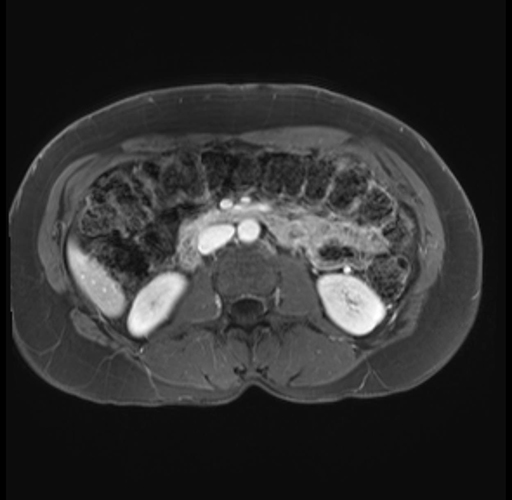

Imaging Analysis

Look through the patient's CT scan to identify any areas of concern for the necessary procedure.

Based on your CT findings, which issue(s) are present and would give reason for "planned slowing down moment(s)" in this case?